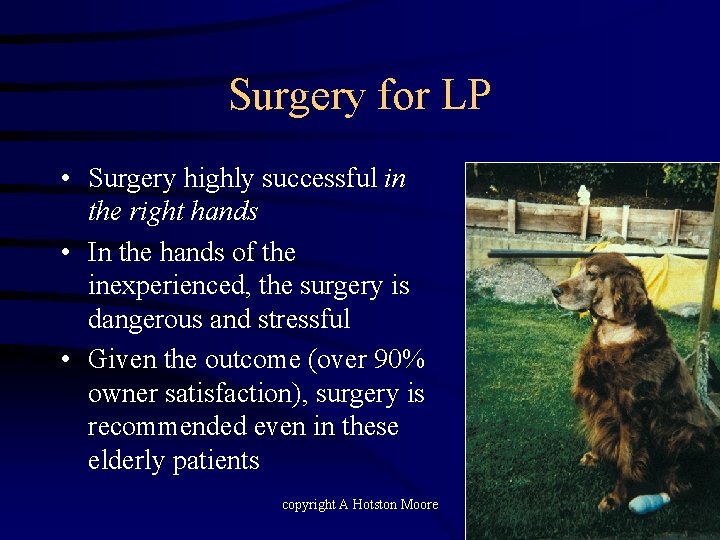

Surgery for LP • Surgery highly successful in the right hands • In the hands of the inexperienced, the surgery is dangerous and stressful • Given the outcome (over 90% owner satisfaction), surgery is recommended even in these elderly patients copyright A Hotston Moore